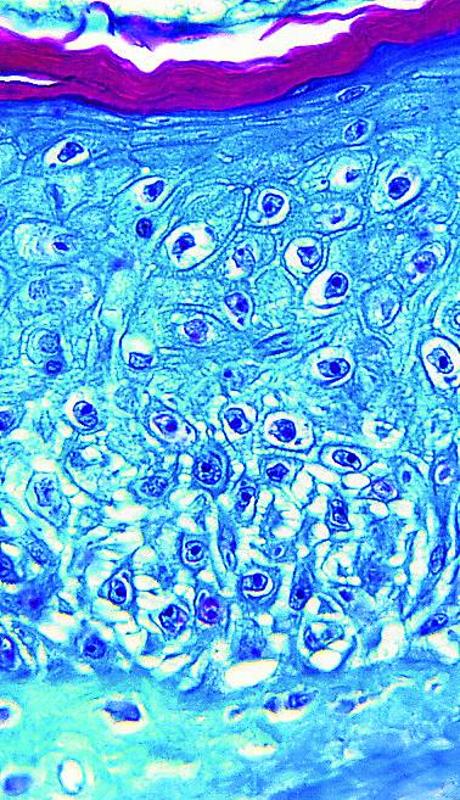

Vigilancia microscópica

El virólogo español Antonio Alcamí participa en el equipo internacional de expertos encargados de analizar el comportamiento de este virus, que se está secuenciando a partir de las muestras extraídas de los pacientes o de cultivos de laboratorio. También está atento al portal web donde los científicos comparten los resultados y cruzan la información en tiempo real. Una de las preguntas que se intenta responder es por qué se propaga ahora con una virulencia desconocida.

Tras analizar el genoma del virus, el investigador del CSIC en el Centro de Biología Molecular Severo Ochoa considera que el virus de la viruela del mono que ahora ataca proviene de África Occidental, de Nigeria. Se trata de la cepa menos severa, comparada con la de África Central. La primera tiene un 1% de mortalidad; la segunda llega al 10%. «Sabemos que es un tipo atenuado del virus, cercano a nivel genético con los que se vieron en Reino Unido en 2018», indica Alcamí. «Tiene unas 50 mutaciones en su código genético. Es decir, de sus 190.000 eslabones ha cambiado 50. Por tanto, no parece, con la información que tenemos hoy, que haya habido una variación en su genoma que justifique un cambio en su comportamiento».

Aunque en 2017 se comprobó en Nigeria que podía haber transmisión de persona a persona, la teoría de la transmisión sexual para la viruela del mono no se había demostrado. Era una posibilidad, al ver que las lesiones cutáneas estaban en las áreas genitales, perianales y bucales, como las de ahora.

Estos factores (en varios lugares, entre numerosos humanos y a través del contacto «piel con piel») muestran un comportamiento nuevo en un virus cuyo efecto se ha multiplicado por diez desde hace medio siglo, cuando se registró en un niño de nueve años, según el artículo científico 'Brote de viruela del mono en Europa, Reino Unido, América del Norte y Australia: una tendencia cambiante de una enfermedad zoonótica', de Beatriz Cabanillas, investigadora del Hospital 12 de Octubre.